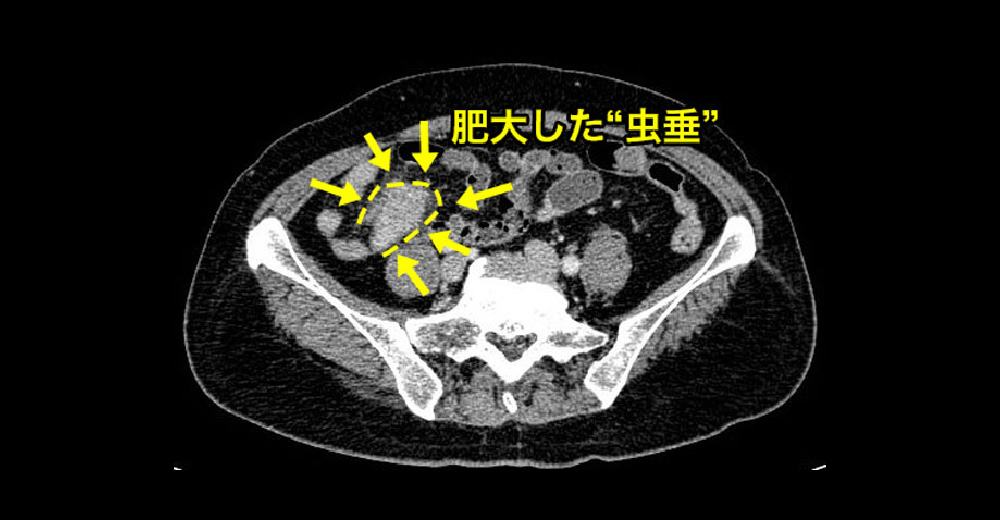

急性虫垂炎 急性虫垂炎 急性虫垂炎

急性虫垂炎 腫大した 虫垂 が造影されています。別症例です。

急性虫垂炎